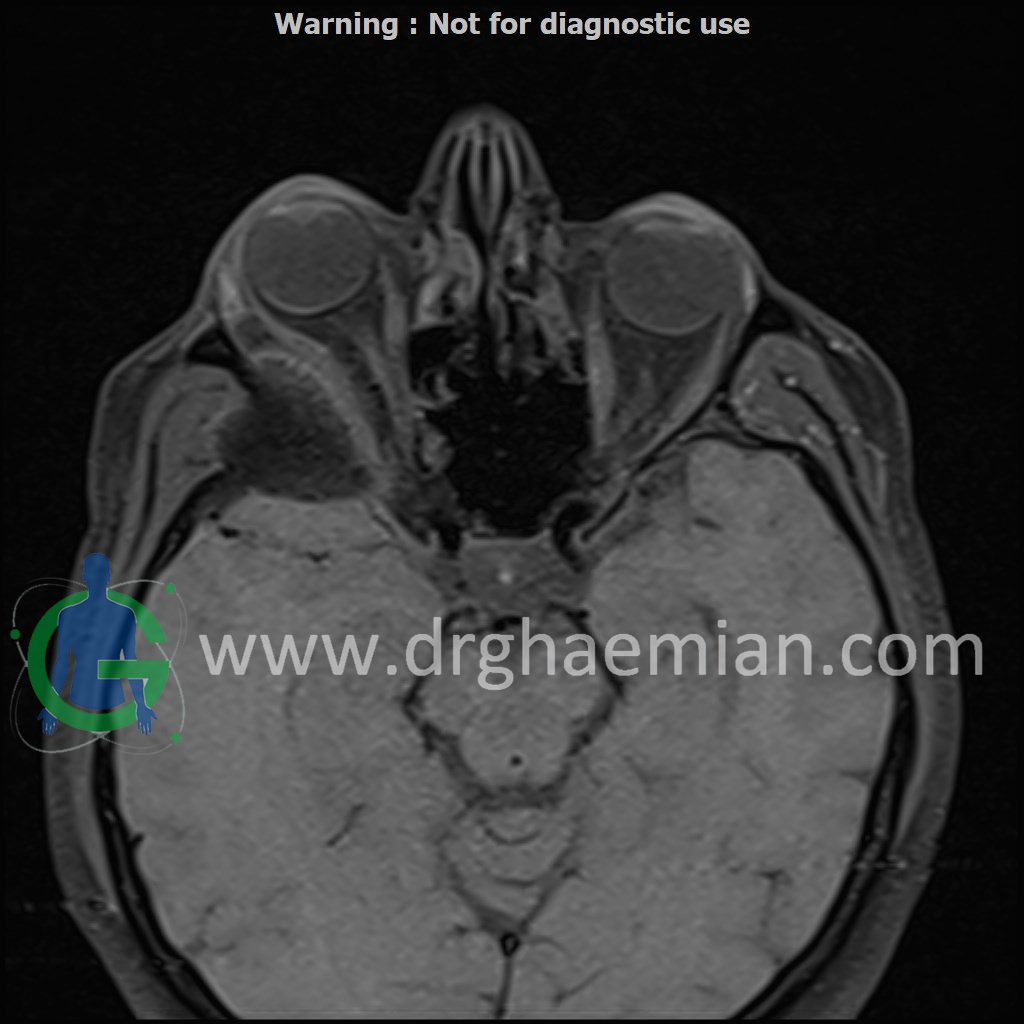

ام آر آی اوربیت با استفاده از آهنربا و امواج رادیویی تصاویری از اوربیت ها، اعصاب، عضلات و بافت های اطراف آن ایجاد می کند. در این کیس مننژیوم مغزی در پشت چشم بیمار دیده میشود.

Technique : Axial T1 , Axial , sagittal , coronal FSE T2 , coronal T1, sagittal fat sat T2 , Axial , sagittal T1 post Gd .

thickening of posterolateral of right orbit wall ( low T1/T2/STIR ) with mass effect on right temporal pole & right orbital content/proptosis , with adjacent dural thickening & post contrast enhancement ( 33x41mm – without significant change to prior MRI – 1403/09/20) suggestive for :

1.meningioma

2.fibrosis plasia with dural thickening & less probably sclerotic bone metastasis